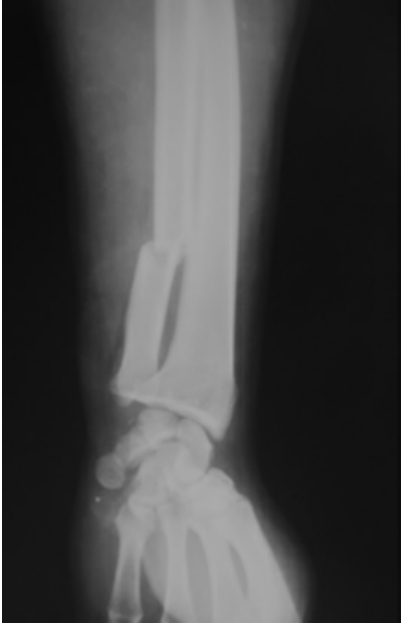

如图7-4-4至图7-4-6即为骨折的影像学检查X线片。

图7-4-4 尺骨骨折当日

图7-4-5 内固定术后

图7-4-6 骨折术后3个月